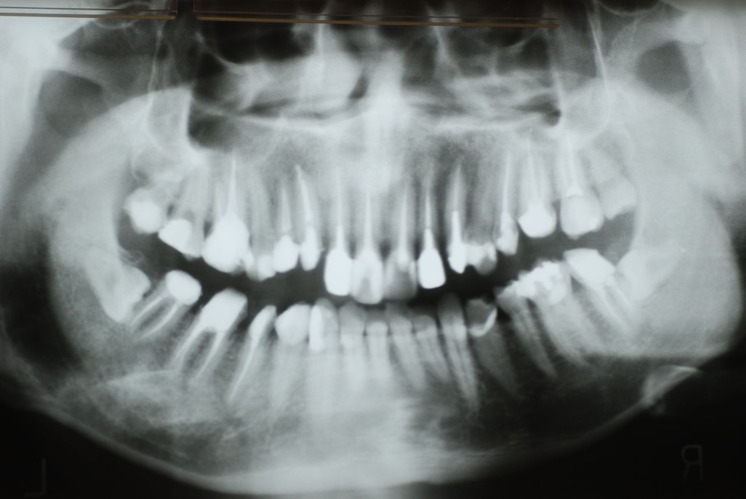

下記は患者に言われるままに血だらけでの不潔な状態で虫歯をとり埋めたようで全然適合していませんし、外れそうになっていました。

外したところです。中は虫歯のオンパレードでした。

適合が悪い銀歯が装着されていて更に虫歯の取残しにより歯髄炎症を起こして神経を取らざるをえなくなりました。神経を除去すれば痛みはなくなります。でもそれは死ぬことなのです。ほぼ寿命は半減したと考えるしかないのです。

まずは掃除の仕方を学ぶべきだったのです。環境をある程度良くしてから治療しないのでほぼ失敗に終わり、またハズレて虫歯により崩壊してしまうのです。